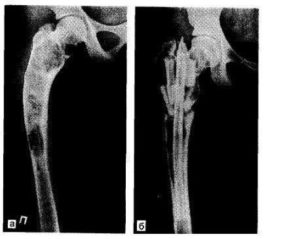

Диагноз «фиброзная дисплазия» ставится после проведения рентгенологического обследования и уточнения анамнеза больного. Как правило, на первоначальном этапе рентгеновские снимки показывают особые области, что по своему внешнему виду напоминают матовое стекло. Расположены они, как правило, на поврежденной кости в районе диафиза или метафиза.

В дальнейшем на пораженной области появляется характерная крапчатая поверхность, на которой происходит чередование уплотнений с небольшими зонами просветления. Кроме того, уже достаточно хорошо просматривается деформация.

- Рентгенологическая картина фиброзной дисплазии разнообразна.

- Патологические участки могут быть то более плотными, то более прозрачными по сравнению с окружающей костью, иногда имеют вид «матового стекла».

- Одни очаги четко отграничены зоной склероза, контуры других расплывчатые, что особенно характерно для костей черепа.

- Нередко выявляются узуры в кортикальном слое, а при наличии перелома — отчетливая периостальная реакция.

- затемнение по типу матового стекла: 56% [1]

- очаг однородный склеротический: 23%

- очаг кистозный: 21%

- очаг с четко определенными границами

- расширение костей с интактными вышележащими костями